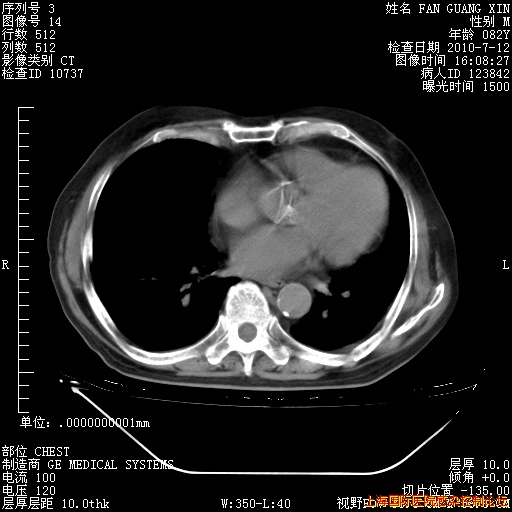

6月12日纵膈窗